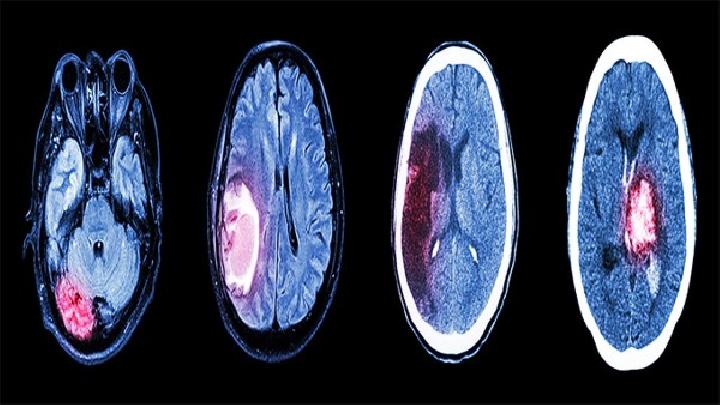

3、利用核磁共振成像(MRI)扫瞄脑部是局限性小脑萎缩的诊断方法之一,可以见到病变进行中的小脑萎缩。